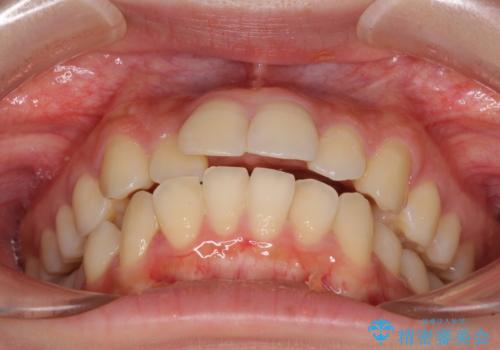

- 口元の閉じにくさを気にして来院された患者様です。

上下ともに歯列が前方に突出していたため、上下左右の第一小臼歯4本を抜去し、ワイヤー装置による矯正治療を行うこととしました。

舌の突出癖による影響もあったため、舌のトレーニングを並行して実施しました。